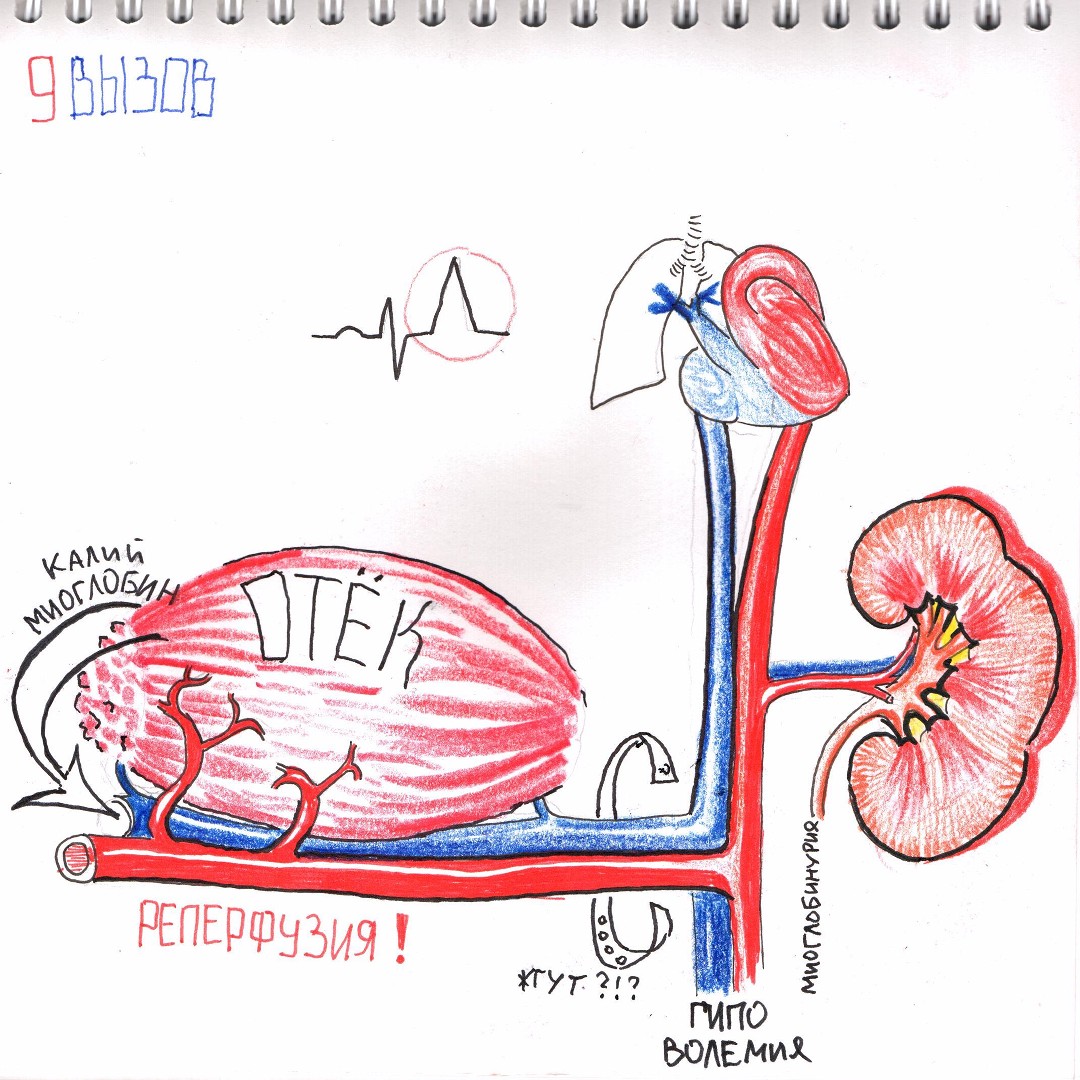

Классификация синдрома длительного раздавливания: основные категории и признаки